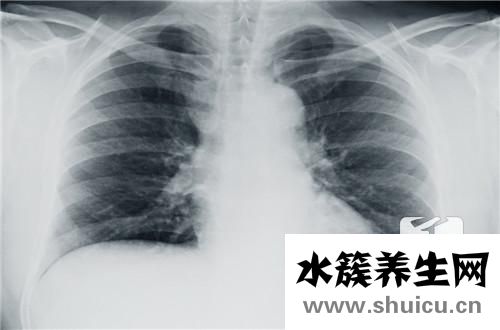

以前都說一個女人可以養活幾千個家庭。的確,如今,女性在日常生活、家庭和工作中的影響力并沒有輸給男性,甚至在某些方面超過了男性。但是隨之而來的是女性的工作壓力越來越大,女性乳房問題越來越嚴重。乳腺疾病已經成為女性的第一大死因。麥默通手術治療是給婦女的乳腺輸血手術治療。

我們都了解乳腺纖維腺瘤是乳腺最普遍良好變病,并且現階段病發群體比較多,一般初期沒有癥狀的,一旦發展趨勢到中后期環節治療方法便是以手術醫治主導。大家常說的這類麥默通手術治療是指乳腺硬塊微創手術無卡旋切機術,手術后采用有效的方法搞好飲食搭配醫護維持心情舒暢,則會加速傷口痊愈。有的病人對這些方面的病癥基本常識掌握的較為少,因此大伙兒平常要保持警惕。